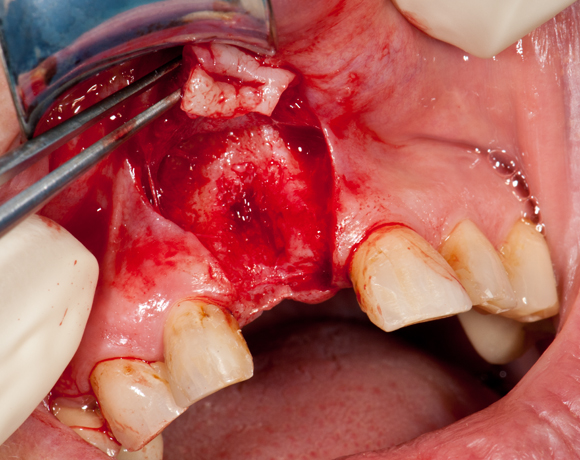

Im vorliegenden Patientenfall sollte ein Implantat für den extrahierten Zahn 11 gesetzt werden. Leider war der vestibuläre Anteil der Alveole des Zahnes 11 bei der Extraktion verloren gegangen. Damit ein ausreichendes Knochenlager zum Implantieren vorhanden ist, musste ein Knochenaufbau gemacht werden.

Bild 04: Eröffnung des OP- Gebietes durch einen Schleimhautlappen